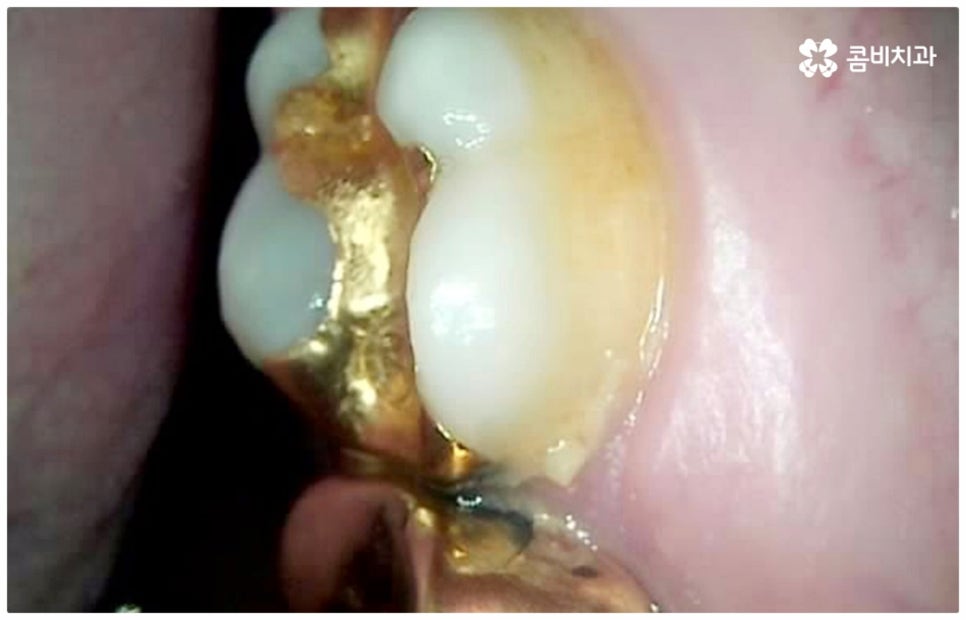

만약 충치가 어느 정도 진행되어 상아질까지 손상되면 비로소 시리거나 쑤시는 듯한 통증이 생기며 이 때 치과에 내원하시면 정도에 따라 감염 부위를 제거하고 어금니충치치료 방법 중 인레이 또는 온레이를 통해 수복하게 되는데, 이 시기를 지나 병증이 더욱 심해지면 내부 치수조직을 제거하는 신경치료를 진행하게 될 거예요.

치아의 가장 겉부분인 법랑질은 인체에서 제일 단단하지만 안쪽으로 들어가면 비교적 무른 상아질과 신경, 혈관이 많이 모여 있는 연조직인 치수가 자리잡고 있으며 만약 이러한 치수가 존재하는 근관 내부가 구강 질환으로 인해 세균에 감염되거나 외부 충격으로 인해 치신경이 노출되어 손상되었을 때에는 근관치료라고도 불리는 신경치료를 통해 이를 치료해 주실 필요가 있습니다. 즉, 세균이나 염증 등으로 돌이킬 수 없을 정도의 손상을 입은 신경을 제거하고 근관을 깨끗하게 소독한 후 빈 공간에 생체친화 충전재를 채워넣어 밀봉한 다음 주변 치아와 높이와 각도 등을 맞춰서 크라운으로 수복을 해주어 남아 있는 자연 치아를 발치하지 않고 보다 오랜 기간 동안 사용할 수 있도록 하는 보존 치료의 일종이 바로 신경치료 및 후속 처치인 크라운 치료인 거예요.